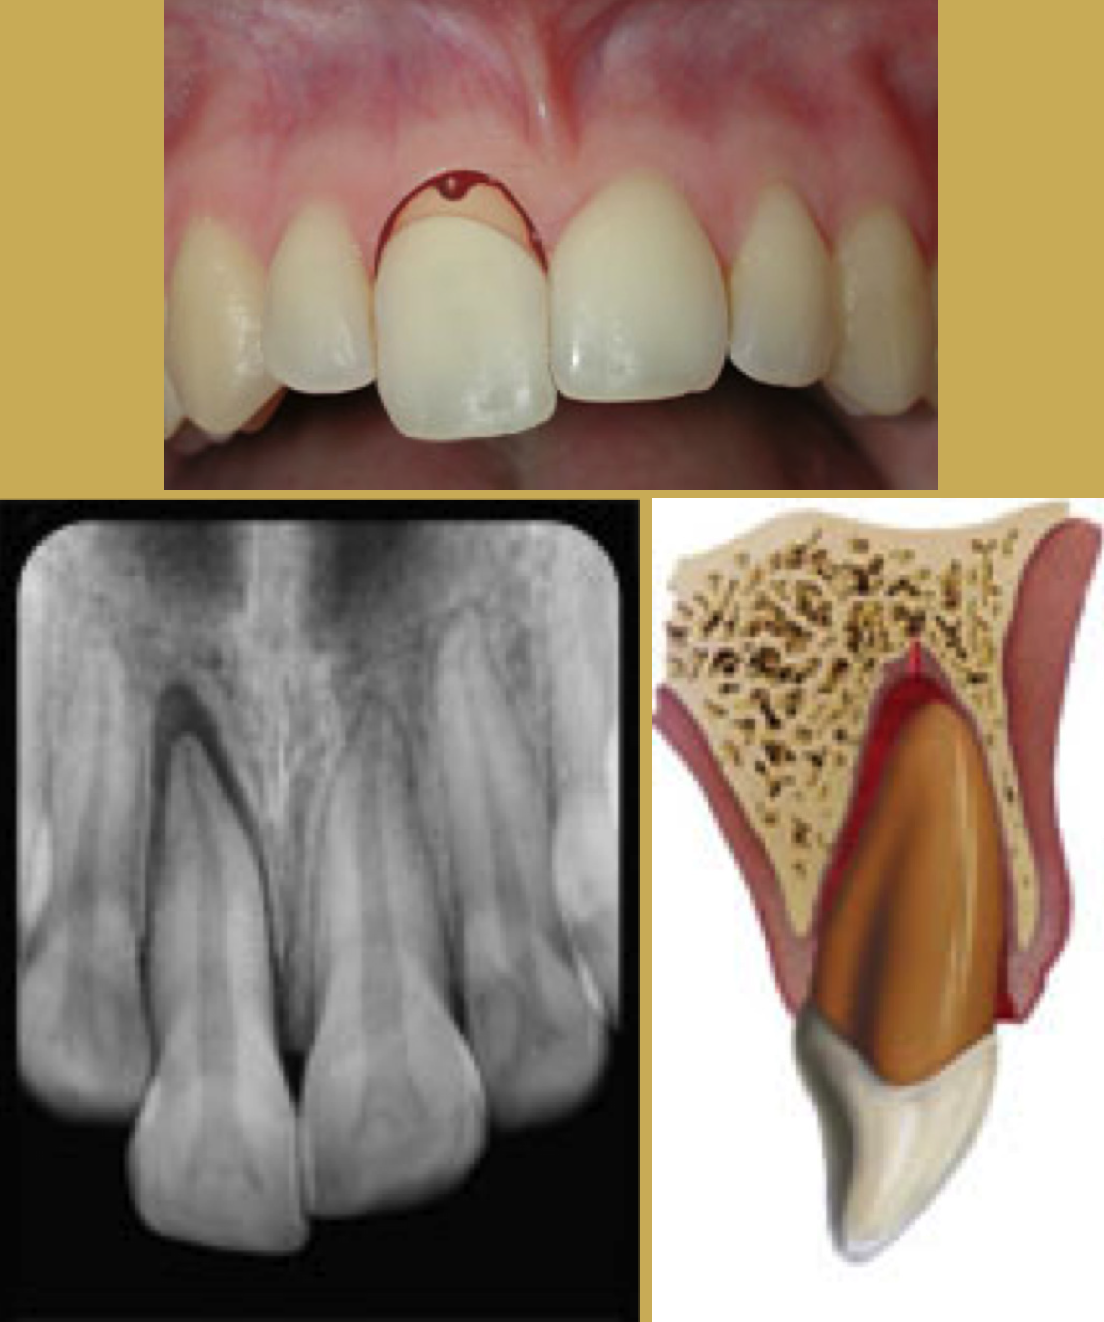

Fig 5. Tooth Fracture

Figure 5

Fig 6. Images of Avulsion

Crown and Root Fractures

Crown fractures (Figure 5) are the most common injury to the permanent dentition and may present in several different ways. The simplest form is crown infraction. This is a crazing of enamel without loss of tooth structure. It requires no treatment except adequate testing of pulpal vitality.14 Fractures extending into the dentin are usually very sensitive to temperature and other stimuli. The most severe crown fracture results in the pulp being fully exposed and contaminated in a closed apex tooth or a horizontal impact may result in a root fracture. The chief clinical sign of root fracture is mobility. Radiographic evaluation and examination of adjacent teeth must be performed to determine the location and severity of the fracture as well as the possibility of associated alveolar fracture.12 Treatment is determined by the level of injury. If the tooth fragment can be located at the scene, it should be placed in a liquid such as water, saline, or milk and sent with the athlete to the dentist.45